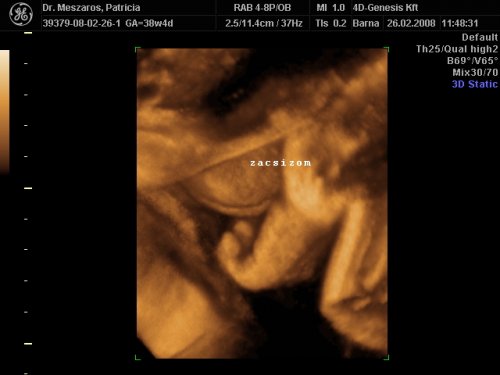

[quote="mpatr"][ írta:mpatrb]Nici, a felvétel élessége és sikerültsége sok mindentől függ.

A profi gépen túl a profi és türelmes szonográfus, a lepény és baba helyzete (mellső fali lepénynél kicsit nehezebb az ügy, meg a babák is imádnak belebújkálni a lepénybe), a magzatvíz mennyisége, a mama hasfalának zsírrétege (mennyire dagi anyuci) szóval ezek (biztos van még) min-mind befolyásolják a felvétel minőségét.

Nekem sikerült ugyanarról a gyerkőcről aki a pocimban van nagyon tuti és nagyon sz..r képet is készíteni ugyanazzal a géppel.

Érdemes többször próbálkozni.